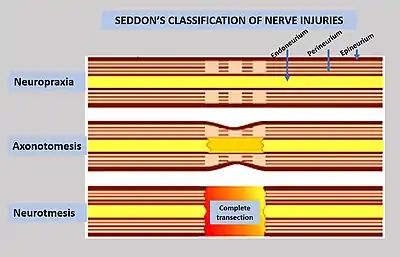

Nerve injury is an injury to nervous tissue. There is no single classification system that can describe all the many variations of nerve injuries. In 1941, Seddon introduced a classification of nerve injuries based on three main types of nerve fiber injury and whether there is continuity of the nerve.[1] Usually, however, peripheral nerve injuries are classified in five stages, based on the extent of damage to both the nerve and the surrounding connective tissue, since supporting glial cells may be involved.[2]

To assess the location and severity of a peripheral nerve injury, clinical assessment is commonly combined with electrodiagnostic tests.[2] Injuries to the myelin are usually the least severe (neuropraxia), while injuries to the axons and supporting structures are more severe (axonotmesis is moderate injury, while neurotmesis is severe injury).[2] It may be difficult to differentiate the severity by clinical findings due to common neurological impairments, including motor and sensory impairments distal to the lesion.[2]

Neurapraxia

Neurapraxia is the least severe form of nerve injury, with complete recovery. In this case, the axon remains intact, but there is myelin damage causing an interruption in conduction of the impulse down the nerve fiber. Most commonly, this involves compression of the nerve or disruption to the blood supply (ischemia). There is a temporary loss of function which is reversible within hours to months of the injury (the average is 6–8 weeks). Wallerian degeneration does not occur, so recovery does not involve actual regeneration. There is frequently greater involvement of motor than sensory function with autonomic function being retained. In electrodiagnostic testing with nerve conduction studies, there is a normal compound motor action potential amplitude distal to the lesion at day 10, and this indicates a diagnosis of mild neurapraxia instead of axonotmesis or neurotmesis.[6]

Axonotmesis

This is a more severe nerve injury with disruption of the neuronal axon, but with maintenance of the epineurium. This type of nerve damage may cause paralysis of the motor, sensory, and autonomic, and is mainly seen in crush injury.[2]

If the force creating the nerve damage is removed in a timely fashion, the axon may regenerate, leading to recovery. Electrically, the nerve shows rapid and complete degeneration, with loss of voluntary motor units. Regeneration of the motor end plates will occur, as long as the endoneural tubules are intact.[2]

Axonotmesis involves the interruption of the axon and its covering of myelin, but with preservation of the connective tissue framework of the nerve (the encapsulating tissue, the epineurium and perineurium, are preserved).[7] Because axonal continuity is lost, Wallerian degeneration occurs. Electromyography (EMG) performed 2 to 4 weeks later shows fibrillations and denervation potentials in musculature distal to the injury site. Loss in both motor and sensory spines is more complete with axonotmesis than with neurapraxia, and recovery occurs only through regenerations of the axons, a process requiring time.

Axonotmesis is usually the result of a more severe crush or contusion than neurapraxia, but can also occur when the nerve is stretched (without damage to the epineurium). There is usually an element of retrograde proximal degeneration of the axon, and for regeneration to occur, this loss must first be overcome.[2] The regeneration fibers must cross the injury site and regeneration through the proximal or retrograde area of degeneration may require several weeks. Then the neuritis tip progresses down the distal site, such as the wrist or hand. Proximal lesion may grow distally as fast as 2 to 3 mm per day and distal lesion as slowly as 1.5 mm per day. Regeneration occurs over weeks to years.[2]

Neurotmesis

Neurotmesis is the most severe lesion with no potential of full recovery.[2] It occurs on severe contusion, stretch, or laceration. The axon and encapsulating connective tissue lose their continuity. The last (extreme) degree of neurotmesis is transsection, but most neurotmetic injuries do not produce gross loss of continuity of the nerve but rather internal disruption of nerve structures sufficient to involve perineurium and endoneurium as well as axons and their covering. Denervation changes recorded by EMG are the same as those seen with axonotmetic injury. There is a complete loss of motor, sensory and autonomic function.[2] If the nerve has been completely divided, axonal regeneration causes a neuroma to form in the proximal stump. For neurotmesis, it is better to use a new more complete classification called the Sunderland System.